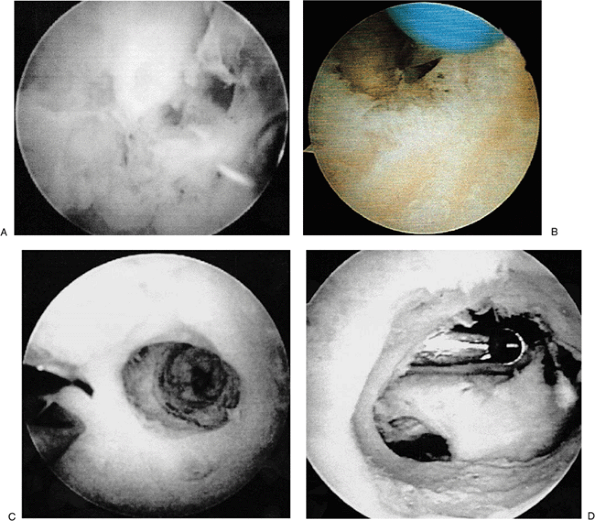

![]() |

Figure 2-12. A: Arthritic radial head. B: Anterior debridement of an arthritic radial head. C: Coplaning through a posterior soft portal of the radial head.

proximal medial portal and the midlateral portal is used for

instrumentation (Fig. 2-12A). The anterior aspect of the radial head is resected to prevent penetration of the anterior capsule. Penetration of the anterior capsule in this area will result in damage to the posterior interosseous nerve.

It is essential that during arthroscopic radial head excision the

anterolateral capsule not be violated by the shaver; otherwise,

significant neurologic complications will occur. Once a majority of the

anterior aspect of the radial head has been excised (Fig. 2-12B),

the inflow is placed in this anterolateral portal and a soft-spot

portal is utilized to bring the shaver from the posterior into the

anterior compartment. This shaver is then used to plane the posterior

aspect of the radial head until it is even with the resected anterior

margin (Fig. 2-12C). In cases of

radiocapitellar impingement this planing is continued for distances of

approximately 6 mm. In cases in which there is proximal radial ulnar

joint involvement, this is continued until the proximal radial ulnar

joint is completely free of the remaining proximal radial head.